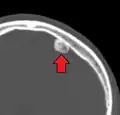

Osteoma